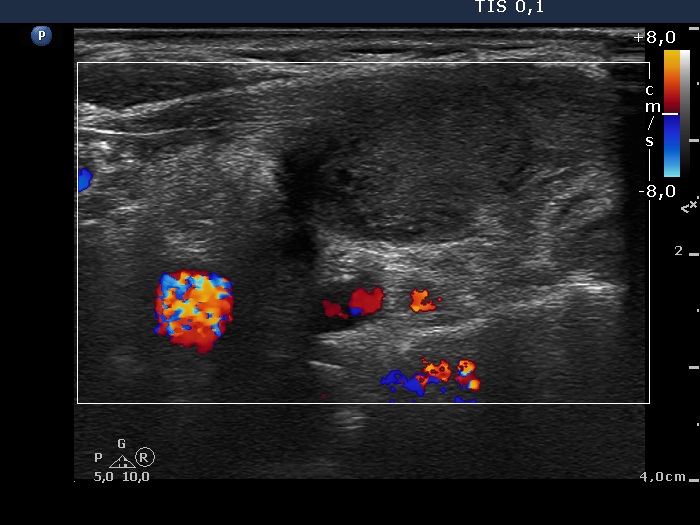

Ultrasonography. There was a moderately hypoechogenic nodule presenting halo sign and perinodular blood flow in the right while two smaller lesions in the left lobe. One of the latter displayed multiple microcalcifications.

The mass in the left side of the neck corresponded to a conglomerate of multiple lymph nodes. These were irregular in shape and presented cystic and necrotic areas. There was no hilum present. The lymph nodes were avascular.